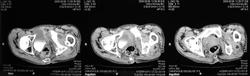

Здесь представлены КТ срезы брюшной полости и таза с контрастированием, выполненные через 2 года после травмы.

Венозная фаза

Реконструкции

на серии кт определяются в средней трети левой почки ,латерально от ее ворот определяется гиповаскулярный участок с четкими ровными контурами .с поддавливанием чашечно-лоханочной системы,ограниченый капсулой почки ,неправильной вытянутой формы ,который в поздней венозной фазе не изменяет своей визуализации (д.д между кистой и кистозной формой почечно-клеточного рака).латерально от левой почки в мягких тканях определяется большой участок со сниженной денситометрической плотностью,размерами - 53х117мм ,с включениями газа и кольцом периферического усиления,с дренажом(вероятнее всего крупный абсцесс).печень увеличена в размере,селезенка с включениями кальция .размеры поджелудочной железы в пределах нормы,холедох и вирсунгов проток без патологии.надпочечники нормальных размеров,без изменений.в области левого тазобедреного сустава определяется участок деструкции с разрушением вертлужной впадины ,головки и шейки бедренной кости ,смещением повздошной кости вверх и латерально на 111.1мм,с фрагментом головки левой бедренной кости .в левой повздошной кости определяются гиперостоз с обширным участком остеосклероза и мелкими участками остеолитической деструкции (смешанный тип).аналогичные остеолитические изменения в крыле правой повздошной кости и в головке правой бедренной кости (сужу по 3d).по медиальному контуру средней трети тела поздошной кости определяется разрушение замыкательной пластинки с вовлечением губчатого вещества на большом протяжении,в крыше и самой вертлужной впадине с мягкотканным компонентом ,с участками пониженной денситометричской плотности (вероятнее всего участки некроза),с мелкими костными фрагментами (что косвенно может подтверждать рост изнутри снаружу),с поддавливанием на большом протяжении органов малого таза,латерально -левая стенка мочевого пузыря утолщена.вывод :такие изменения могут быть как первичного так и метастатического характера .первопричина протрузии возможно врожденного характера(дисплазия) ,затем перелом усугубил процесс(посттравматическая протрузия).меня настораживает тот момент,что изменения в повздошной кости напоминают хронический остемиелит изначально .а затем появились изменения ,сильно напоминающие озлакочествление+изолированно крупный абсцесс